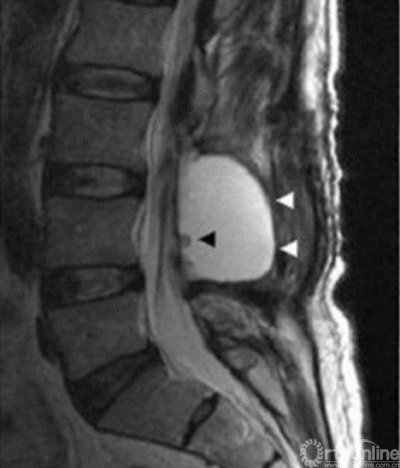

假性硬膜外膨出2

2. D. L. Marinus Oterdoom, Rob J. M. Groen, Maarten H. Copes. Cauda equina entrapment in a pseudomeningocele after lumbar Schwannoma extirpation[J].

Eur Spine J 2010;19: 158–161.